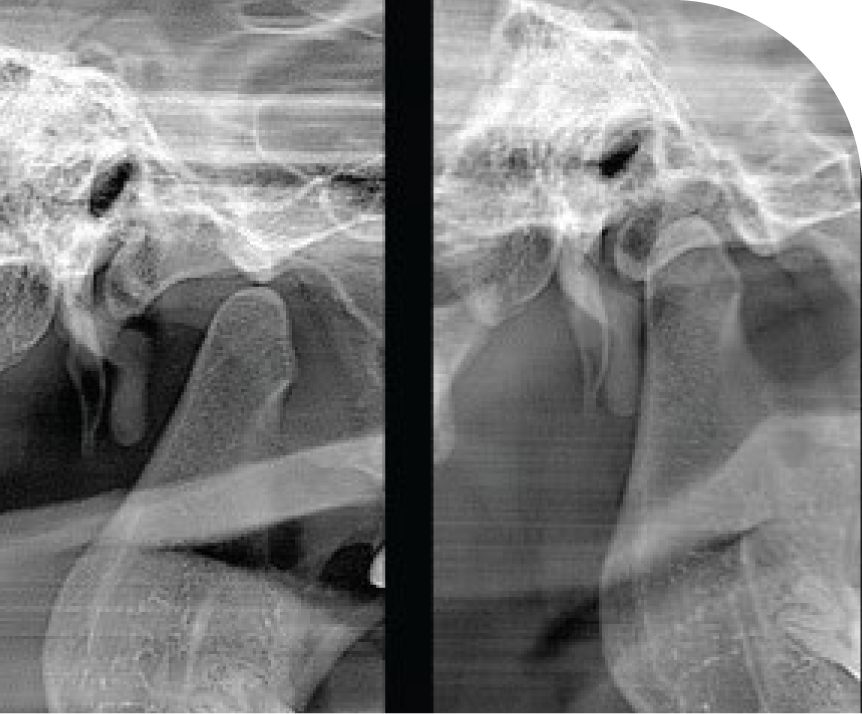

TMJ

Diagnostic and Treatment Support

Enhance your practice with our specialised TMJ imaging services. We provide advanced diagnostic imaging, including X-Rays and CT scans, to support the accurate diagnosis of temporomandibular joint disorders. Our high-quality imaging aids you in developing effective treatment plans, helping to alleviate patient discomfort and improve jaw function. Partner with us to offer your patients the highest standard of care in TMJ disorder management.